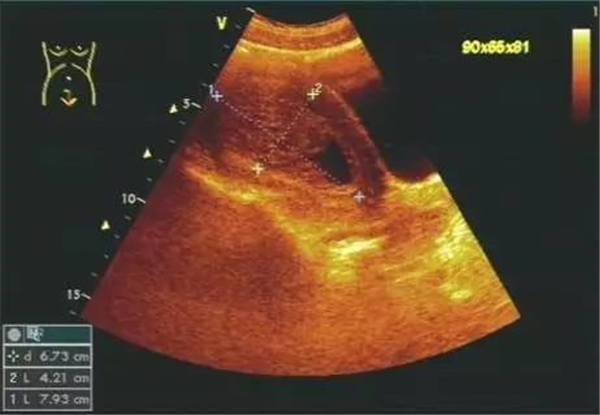

聲像圖特點:1、子宮增大邊界不規則。2、肌瘤結節呈低回聲、等回聲或強回聲。等回聲周邊可有低回聲暈呈假包膜。3、子宮內膜移位或變形。4、膀胱變形,易引起尿貯留。5、肌瘤結節周圍呈環狀及半環狀血流。阻力指數0.6±0.1。

聲像圖特征:1、子宮均勻性增大,邊界規則。2、子宮內膜線前移。3、子宮內回聲不均勻,低回聲、強回聲區,無包膜。4、子宮大小、內部回聲月經前后常有變化。5、腫塊周圍無環狀或半環狀血流,阻力指數約0.6。